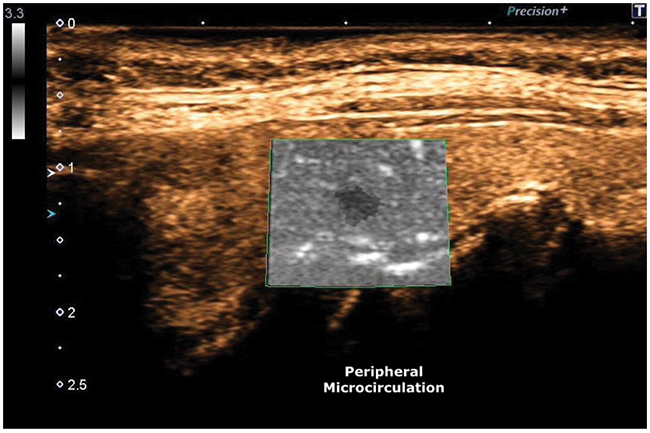

Figure 7: ADF, Peripheral Microcirculation.

The tumor characteristics of the “Black Ink”, highlighted in this case report, provides a reliable prognostic classification, in order to define an effective therapeutic plan.

Thyroid cancer is among the most common cancers in women. We described a case of a 58-year-old woman with a Ø 0.3 cm “Black Ink” image, which was subjected to FNAC and cytology examination and treated with total thyroidectomy with subsequent histology report of papillary thyroid microcarcinoma (invasive type). Ultrasonography together with FNAC have proven to be the most sensitive diagnostic imaging techniques for the early diagnosis of this thyroid neoplasm.

We are convinced that, despite the very small size of this micro-lesion, Black Ink echopattern represents a very important biological risk factors and that size, actually, has a serious consideration in malignancy assessment.